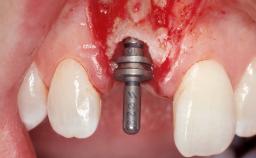

Late Placement of an Implant in a Maxillary Left Central Incisor Site

A 36-year-old female patient was referred for the replacement of the upper left central incisor (tooth 21), which had fractured. Although the tooth had been asymptomatic for many years, the crown began to loosen, at which time she presented to her dentist for an assessment. Teeth 21 and 22 had both been endodontically treated many years previously. She was a healthy individual and a non-smoker.

| Bone Augmentation | Horizontal|Staged |

| Augmentation Materials | Xenogenous|Membrane |

| Soft Tissue Grafting | Simultaneous |